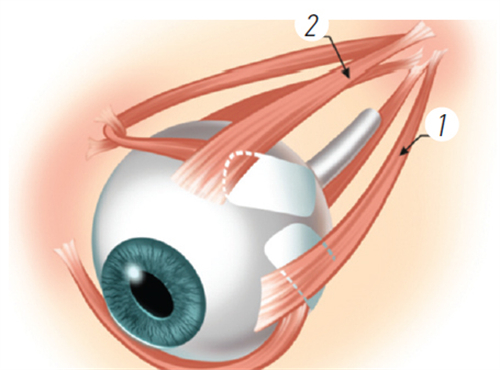

然而,手术并非一蹴而就。在决定进行手术之前,患者需要进行多方面的眼部检查和评估。医生会对患者的角膜厚度、眼底情况、视网膜健康状态等进行详细检查,以评估手术的风险和可行性。这些检查有助于医生确定适合患者的手术方式和术后护理方案。

对于高度近视患者而言,眼底检查尤为重要。因为高度近视往往伴随着眼底病变的风险,如视网膜变性、裂孔、黄斑区病变等。如果患者的眼底情况不稳定或存在重度病变,可能需要可靠行干预治疗,待眼底情况稳定后再考虑手术。